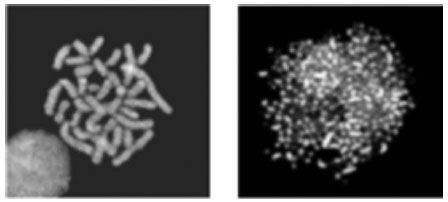

O potencial de letalidade desse complexo aumenta drasticamente quando se iniciam os mecanismos de replicação ou as tentativas das helicases em desobstruir a interrupção criada pelo complexo enzima/inibidor na fita de DNA. Isto converte as quebras transitórias das fitas em permanentes, que já não são mantidas juntas por pontes proteicas. Estas pausas prolongadas geram uma série de eventos, tais como a produção de aberrações cromossômicas. Quando esses fragmentos permanentes de DNA estão presentes em concentração suficiente, inicia-se uma série de eventos que culminam na morte celular por apoptose (Figura 15).44,45

Figura 15. Células normais e células tratadas com etoposide - cromossomos extensivamente fragmentados no tratamento com etoposide45